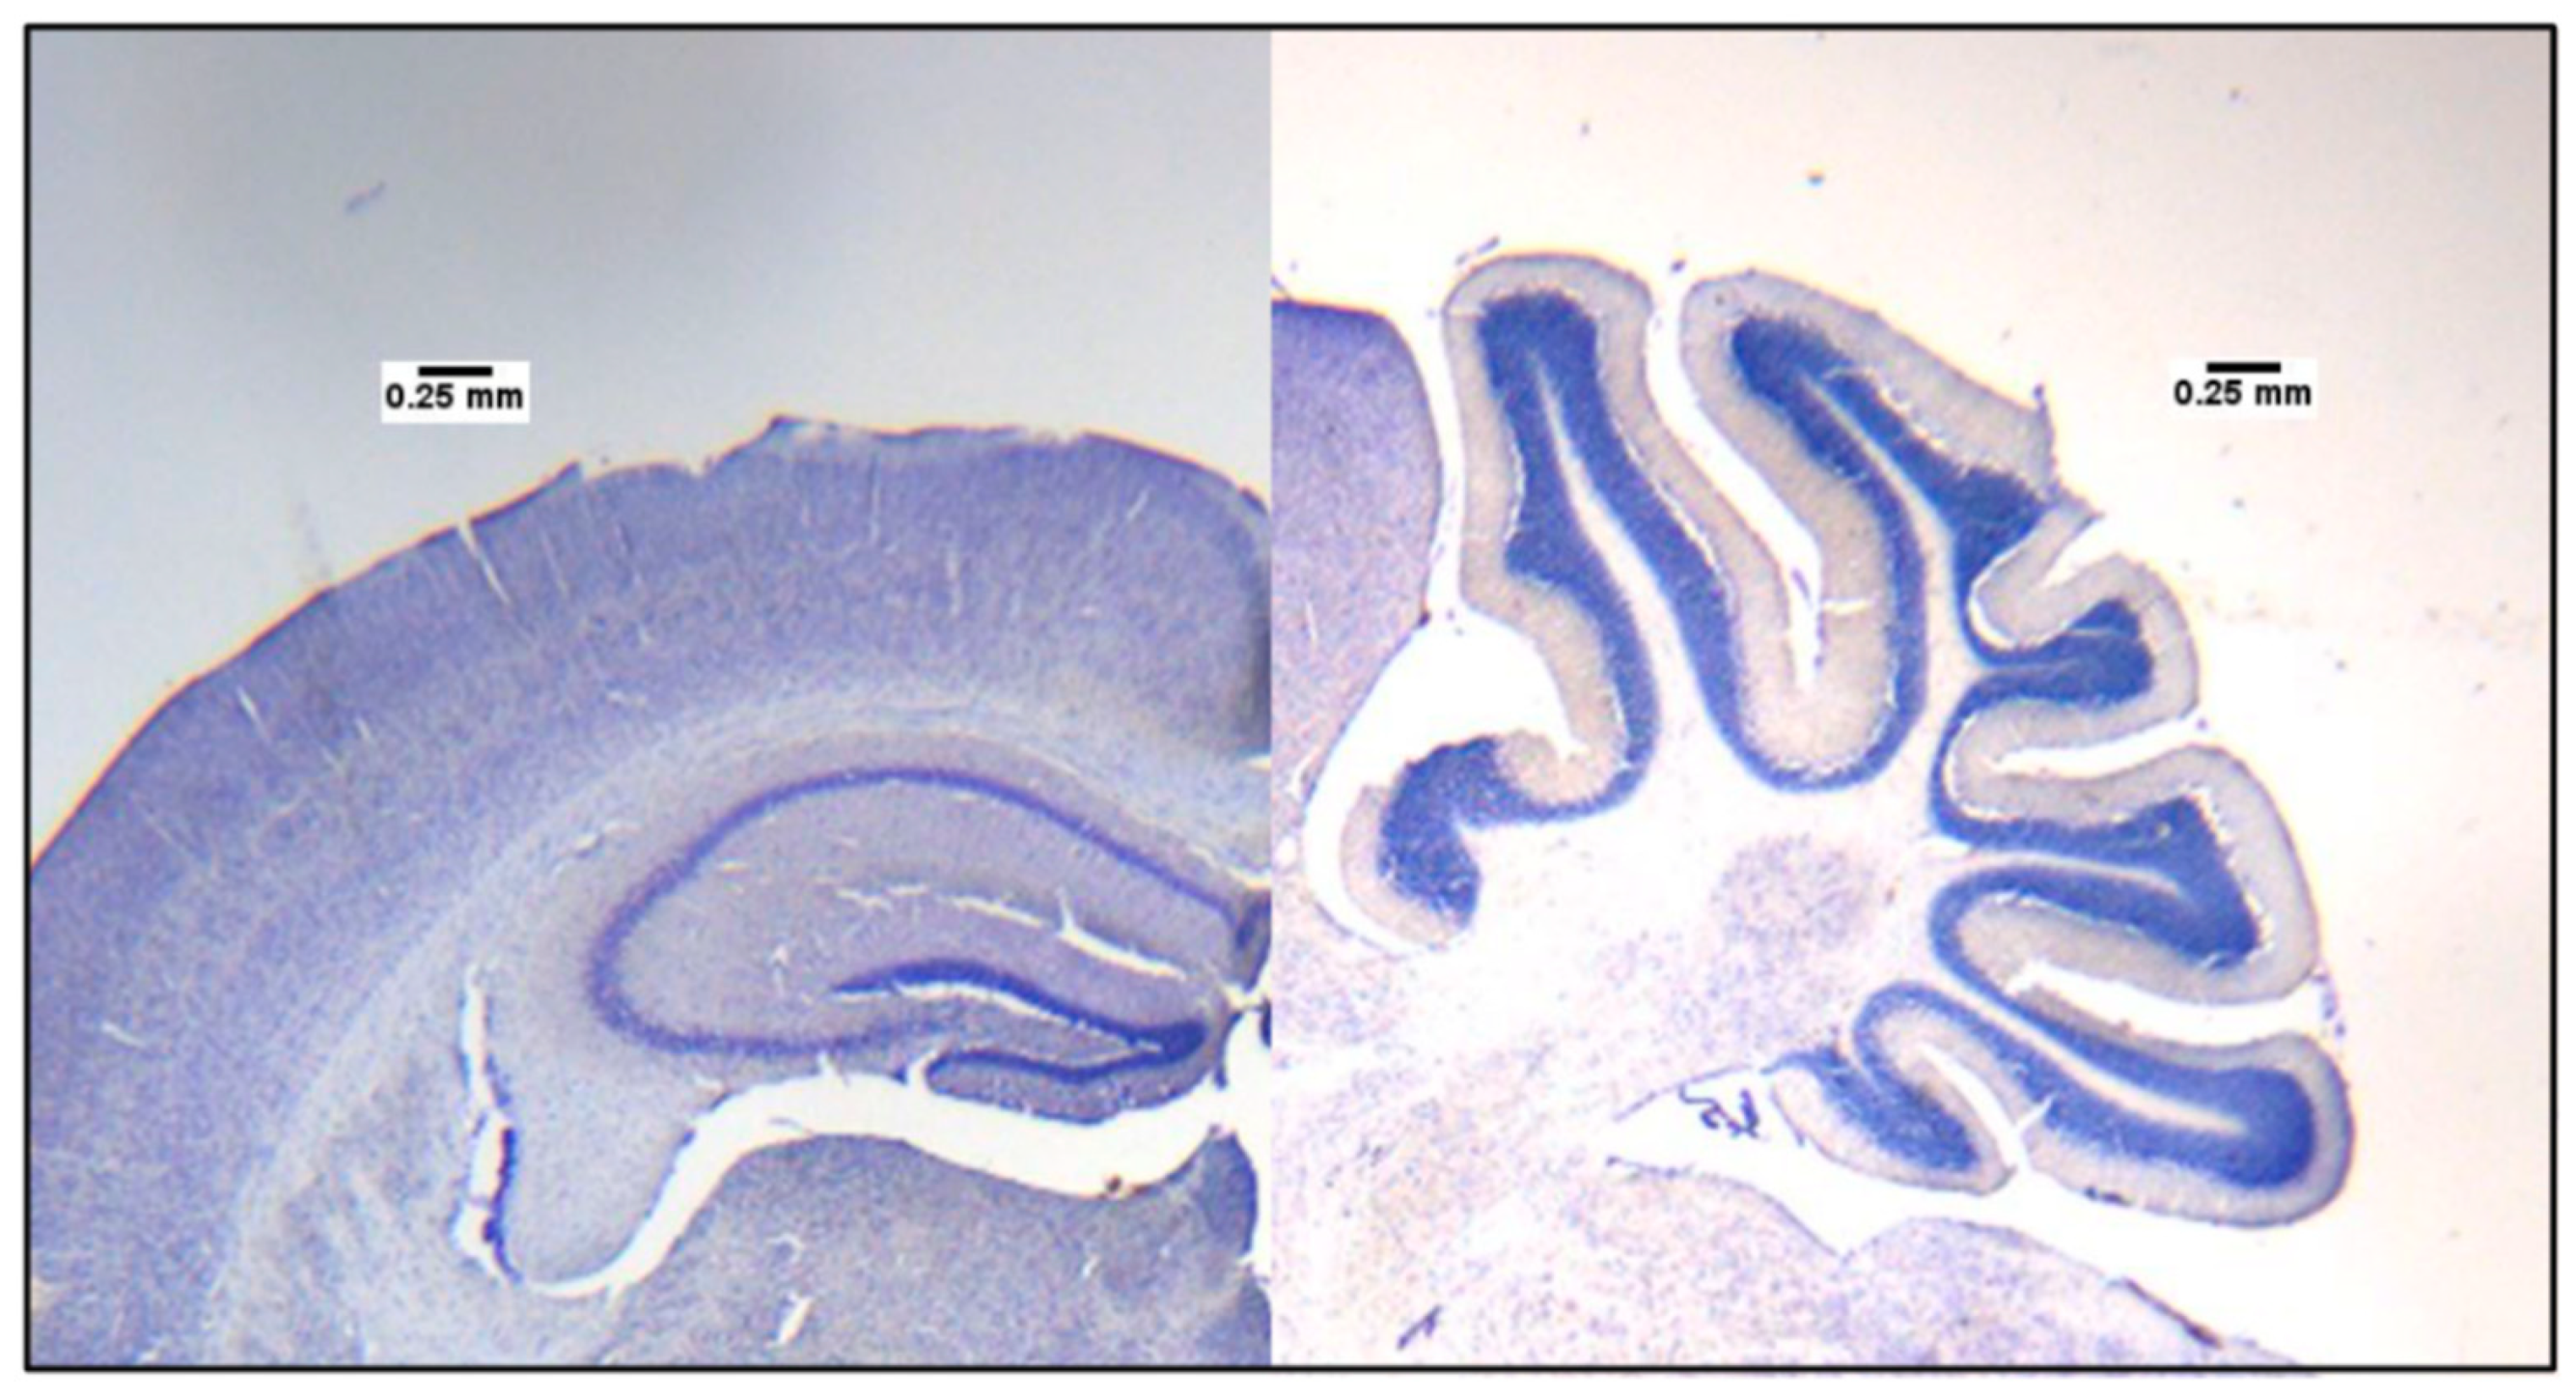

3.6. Hippocampus and Cerebellum Size Differences between Control and TgSwDI Mice